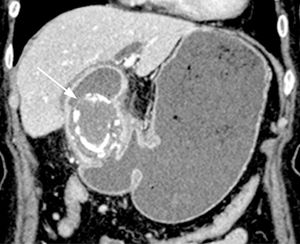

Figure 2.

Endoscopic appearance of the impacted gallstone in the first portion of the duodenum, resulting in complete gastric outlet obstruction.